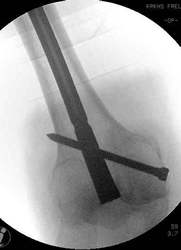

Ein Femurnagel wurde so zugerichtet, dass mit ihm die Prothesenspitze in einer Länge von 8 cm aufgefädelt wurde. Der Nagel wurde durch das Knie hindurch eingebracht. Distal wurde der Nagel verriegelt. Belastungsstabilität lag vor.